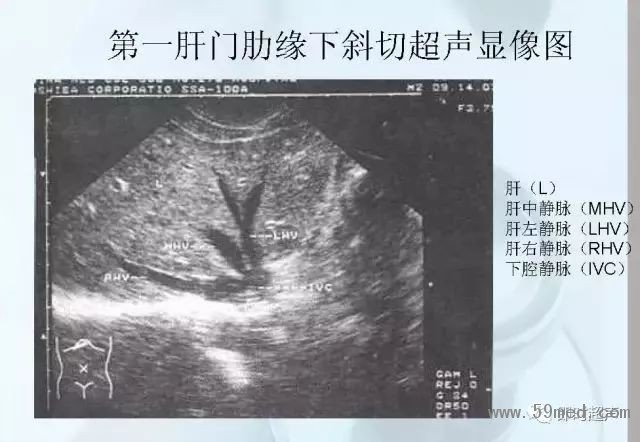

![]() ![]() ![]() ![]() ![]() ![]() ![]() ![]() ![]() ![]() ![]() ![]() ![]() ![]() ![]() ![]() ![]() ![]() ![]() ![]() ![]() ![]() ![]() ![]() ![]() ![]() ![]() ![]() ![]() ![]() ![]() ![]() ![]() ![]() ![]() ![]() ![]() 【注:本文來源于即時超聲,版權(quán)歸原作者所有,如有侵權(quán) 請聯(lián)系 速刪】 =========================== 【閱精彩*悅分享】隨手點擊轉(zhuǎn)至朋友圈,與大家一起分享精彩資訊!當(dāng)然您也可以通過以下方式找到我,與您共同分享藍(lán)韻影像超聲的更多精彩!微信號:landultrasound 電話:+86-0755-66869896 24小時客服熱線:400-888-6452